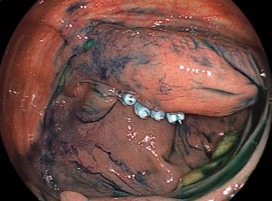

症例2:便潜血検査2回法で、2回陽性で受診。SD junction(S状結腸と下行結腸の境界)に腫瘍サイズ30mmの大型の有茎性(くきを有する病変)の隆起性病変を認め、日帰りにて内視鏡的粘膜切除術(EMR)で切除しました。

境界部に非常に存在する大型の腫瘍であったため、視野確保が困難でした。拡大内視鏡で、「がん」を疑うVI型ピットパターンを認めましたが、診断的治療目的で内視鏡的粘膜切除術(EMR)を施行しました。

一つの視野で全貌が追えないレベルの非常に太くて長い茎を有しているので、出血のリスクが高いのは内視鏡医なら即座に理解するでしょう。

操作性不良部位であることと、腫瘍が屈曲部にはまりこむようなポジションで、局注後も術野の確保に苦慮しました。

切除後の潰瘍底:切離直後の出血は、認めなかった。

最大径30mmの「早期大腸がん」で深達度は:粘膜下層;head invasion(頭部浸潤)、脈管侵襲:陰性、簇出:low、切除断端陰性であった。術後の後出血も認めなかった。